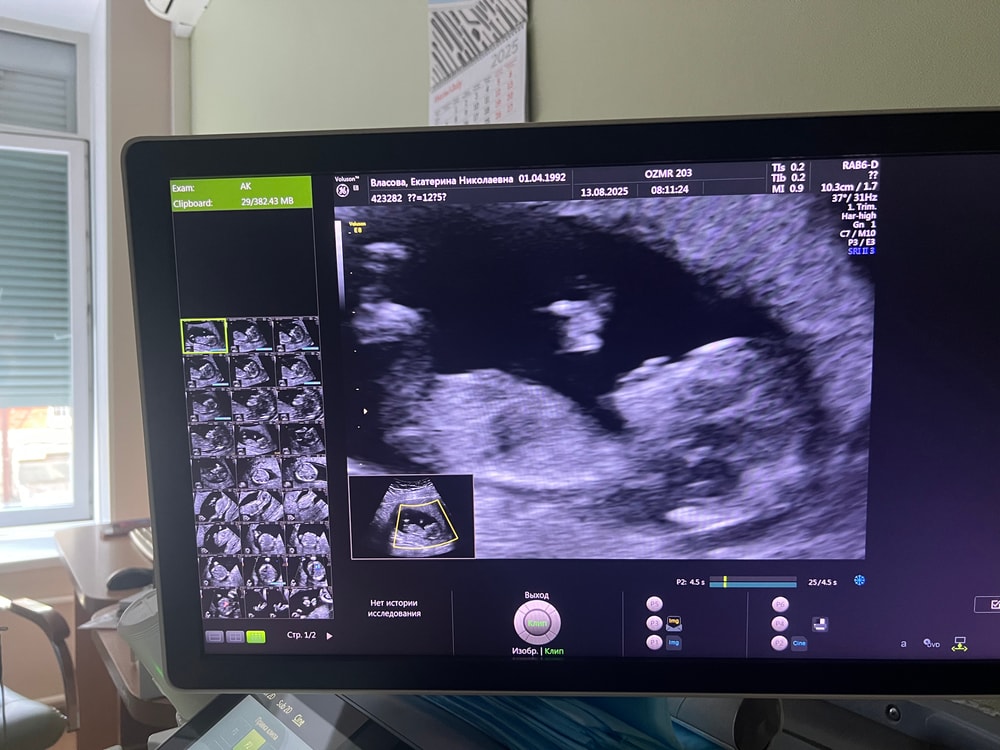

Анализы, скринингиСегодня был первый скрининг. Ктр 58 мм. Без каких-либо изменений и осложнений. Носовая кость визуализируется. И да, пришел ответ на мой вопрос по НИПТ кто же там живет) Вероятность с 97% пол плода женский.

Сегодня был первый скрининг. Ктр 58 мм. Без каких-либо изменений и осложнений. Носовая кость визуализируется. И да, пришел ответ на мой вопрос по НИПТ кто же там живет) Вероятность с 97% пол плода женский.